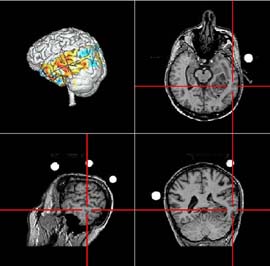

Die sogenannte „Neuronavigation“ ermöglicht die Übertragung der Struktur- und Funktionsdaten auf die für jeden Patienten individuelle Operationssituation. Sie leitet den Operateur wie Sie es vielleicht durch Satellitennavigationstechniken in modernen PKW's kennen.

Mit Hilfe einer neuartigen Untersuchungstechnik, der sogenannten „funktionellen Kernspintomographie“, ist es möglich bereits vor der OP wichtige Bereiche wie Sprache und Bewegung auf der Hirnoberfläche zu lokalisieren.

Für die Sprache wichtige Areale werden hierbei rot dargestellt. Anhand dieser Bilder kann nun der operative Eingriff sicher geplant werden.